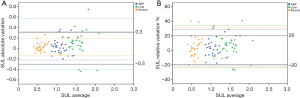

The ICCs for the ABP, liver, and muscle were 0.65 (95% CI, 0.38–0.81), 0.47 (95% CI, 0.15–0.70), and 0.82 (95% CI, 0.65–0.91), respectively. The M-SUL ICC was higher than that of the liver (P=0.02). The ABP-SUL ICC tended to be higher than that of the liver but was not significantly different (P=0.33). The ABP-SUL, L-SUL, and M-SUL CVs were 9%, 12%, and 10%, respectively. In the Bland-Altman plots (Figure 2), 23% (7/30) of the absolute variations and 23% (7/30) of the relative variations in the L-SUL were found outside the permitted variation limits by PERCIST. These numbers were 10% (3/30) and 10% (3/30) for the ABP-SUL, and 0% (0/30) and 7% (2/30) for the M-SUL, respectively.